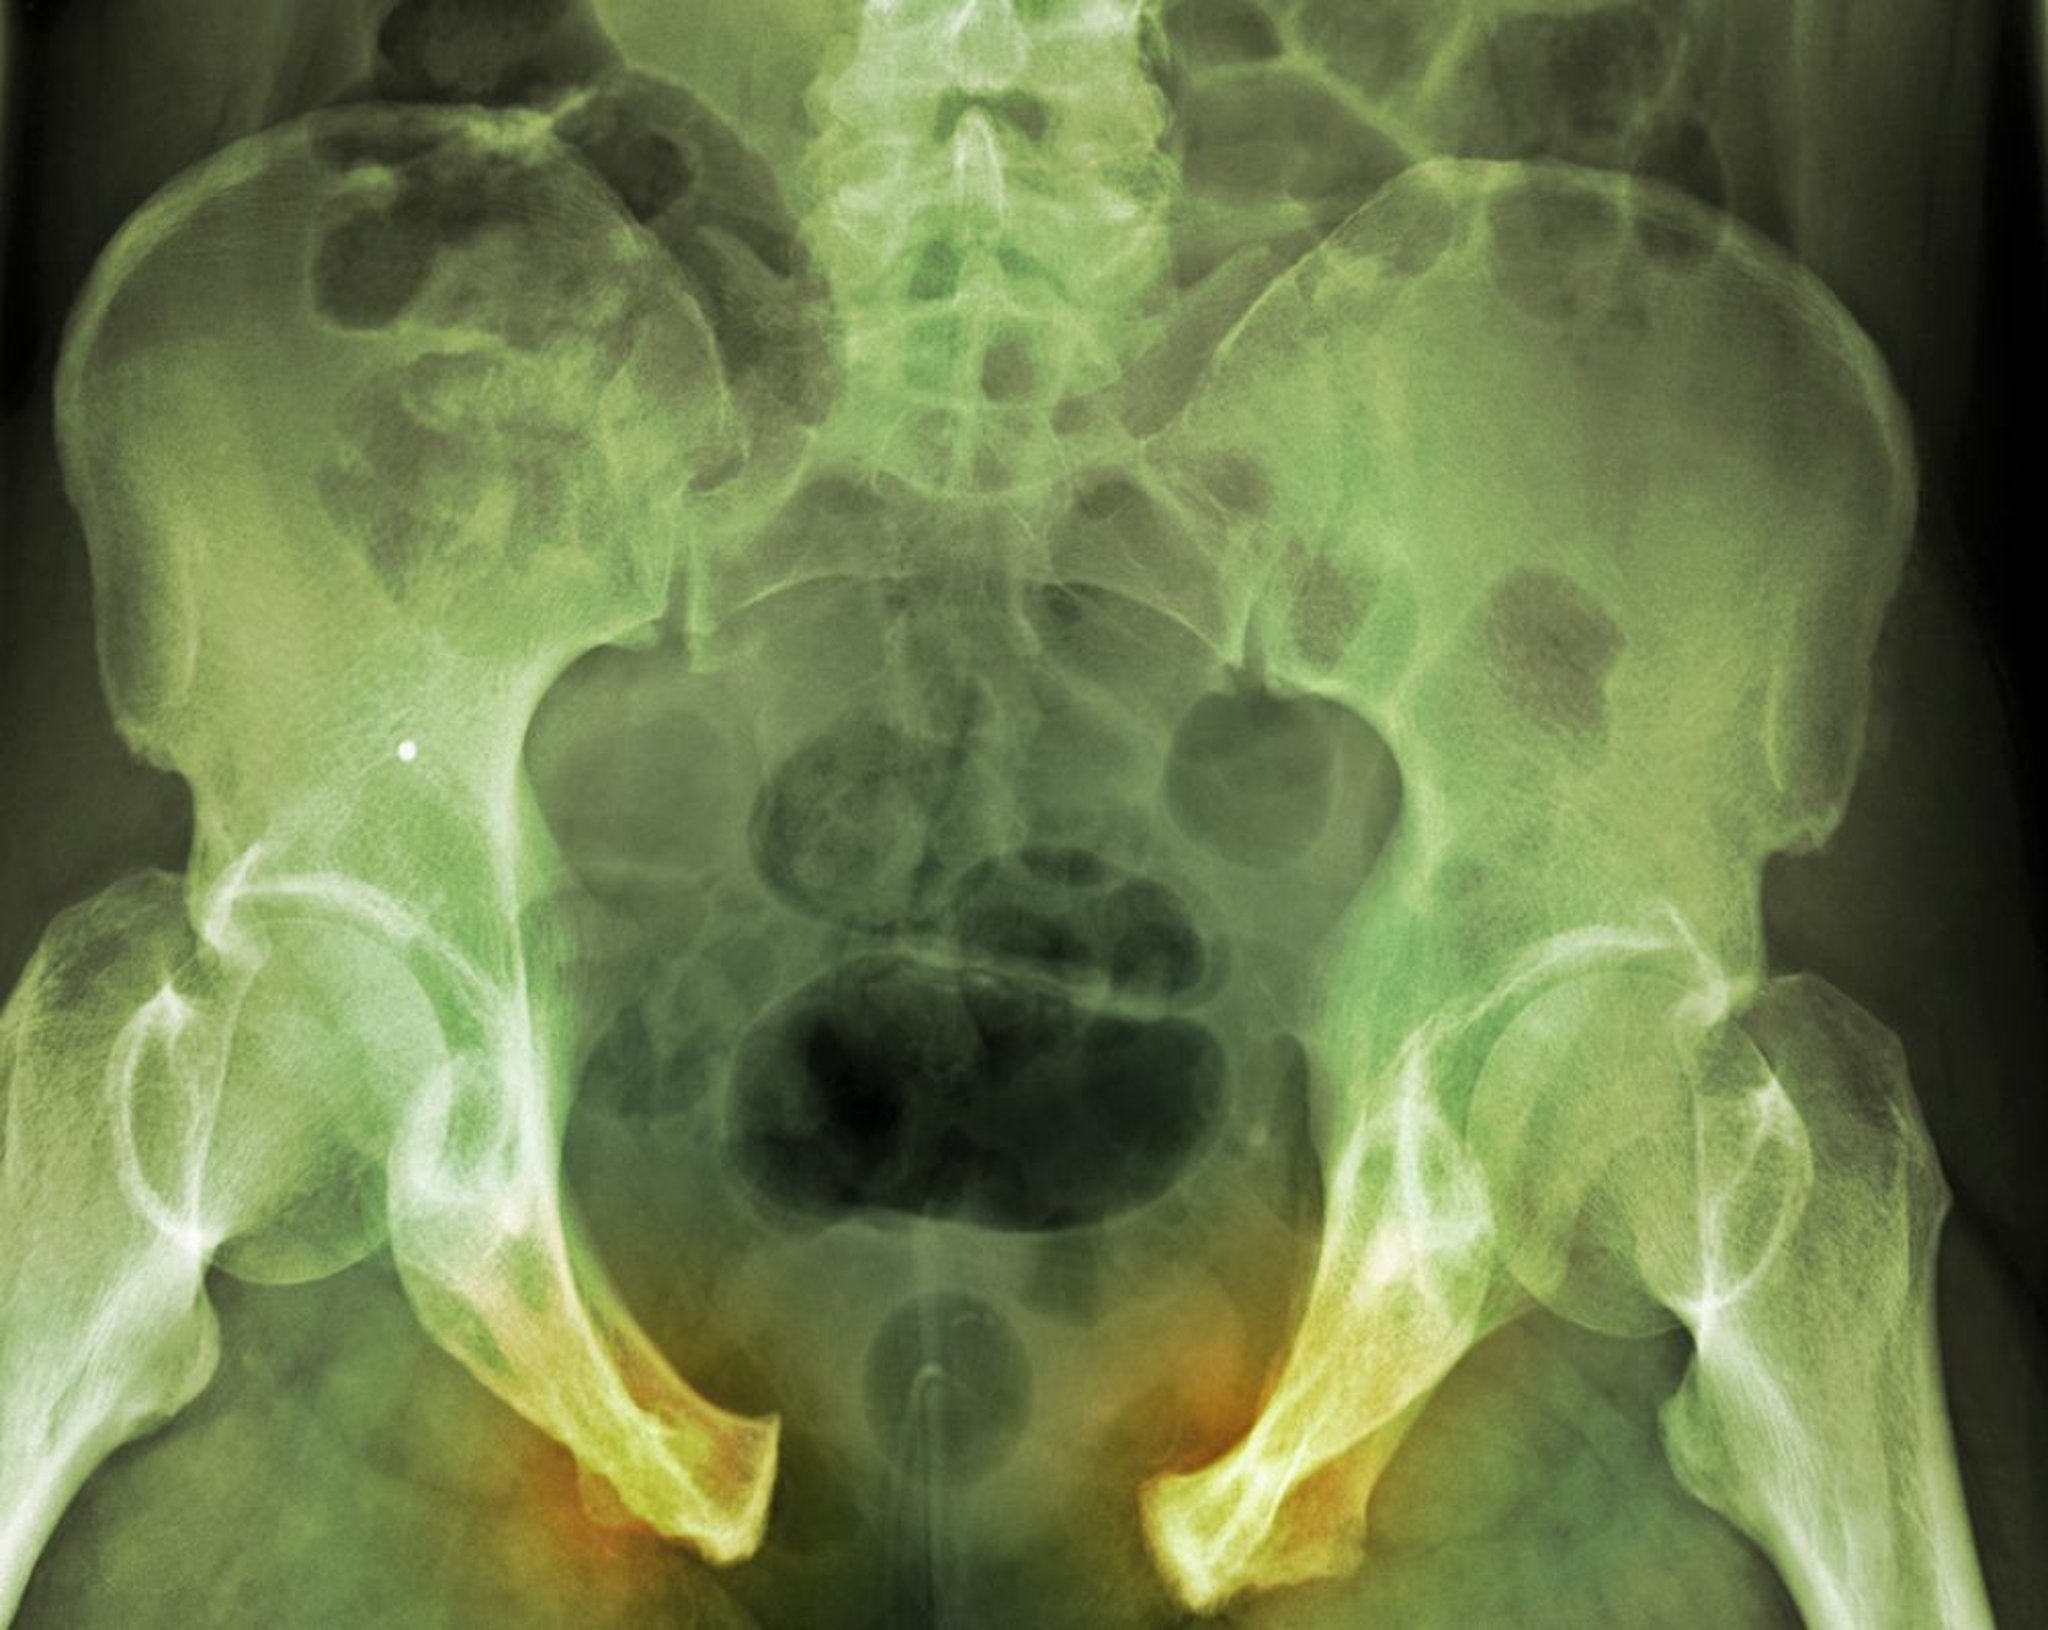

Beckenfraktur

Bei dieser schweren Verletzung ist die Unterbrechung des Beckenrings anhand der weit auseinander liegenden Schambein-Syndesmose und der rechtsseitigen Iliosakralbänder deutlich erkennbar. Frakturlinien sind nicht so offensichtlich.

DU CANE MEDICAL IMAGING LTD/SCIENCE PHOTO LIBRARY